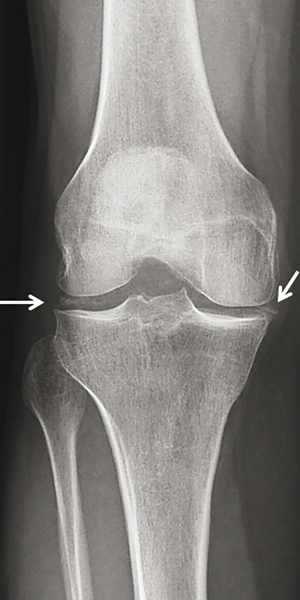

© Gérard Chalès, Pascal Guggenbuhl (La Revue du Praticien)

Radiographie de genou de face. Calcifications méniscales bilatérales. Voir : Guggenbuhl P, Coiffier G, Albert JD, Chalès G. Dossier. Arthropathies microcristallines. Rev Prat 2015;65(5):665-82.